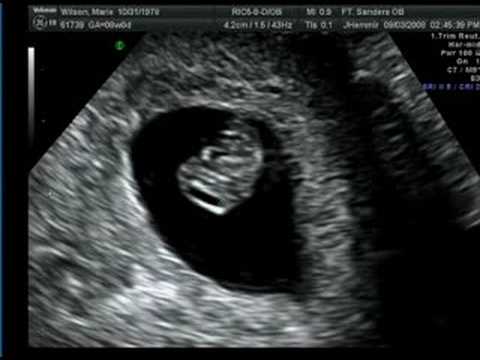

Kết quả siêu âm thai 7 tuần sẽ cho thấy khuôn mặt của thai nhi cũng có sự biến đổi nhỏ, mắt phát triển với kích thước lớn hơn, phần tai đã dần nhô ra và hình thành cấu tạo căn bản.

Thai nhi 7 tuần tuổi đã có những bước phát triển nhất định cả về hình dáng bên ngoài cũng như các chức năng bên trong của cơ thể. Chính vì thế, đây là giai đoạn thích hợp để mẹ bầu tiến hành siêu âm hình ảnh thai nhi và kiểm tra quá trình phát triển của bé yêu. Hình ảnh siêu âm thai 7 tuần tuổi sẽ cho biết nhiều chỉ số sức khỏe quan trọng giúp mẹ hình dung rõ ràng, cụ thể mức độ phát triển của bé yêu vào thời điểm này.